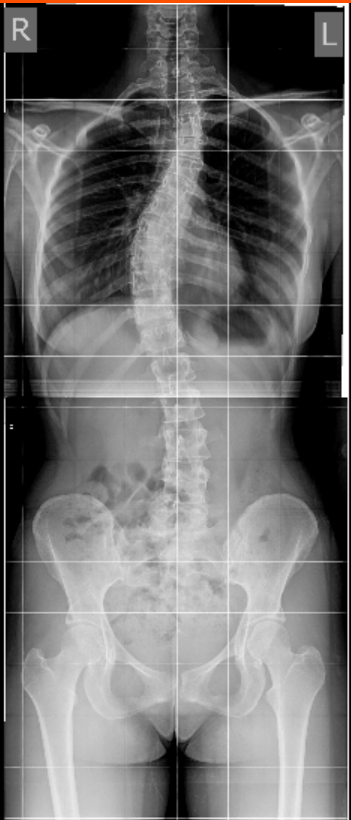

Спустя 11 месяцев от первой операции конструкция наклонились вбок, прогрессировала верхняя дуга. Справа результат после второй операции в клинике Пирогова.